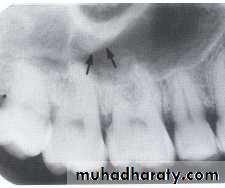

NUTRIENT CANALS

:

Nutrient canals carry a neurovascular bundle and appear as radiolucent lines of fairly uniform width. They are most often seen on mandibular periapical radiographs running vertically from the inferior dental canal directly to the apex of a tooth or into the inter dental space between the mandibular incisors.